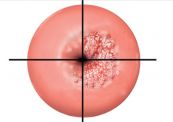

Loạn sản cổ tử cung là một tình trạng phổ biến, xảy ra ở phụ nữ dưới 30 tuổi và thường gắn liền với các bệnh lây truyền qua đường tình dục. Để hiểu rõ hơn về bệnh lý này, mời các bạn tham khảo bài viết dưới đây!